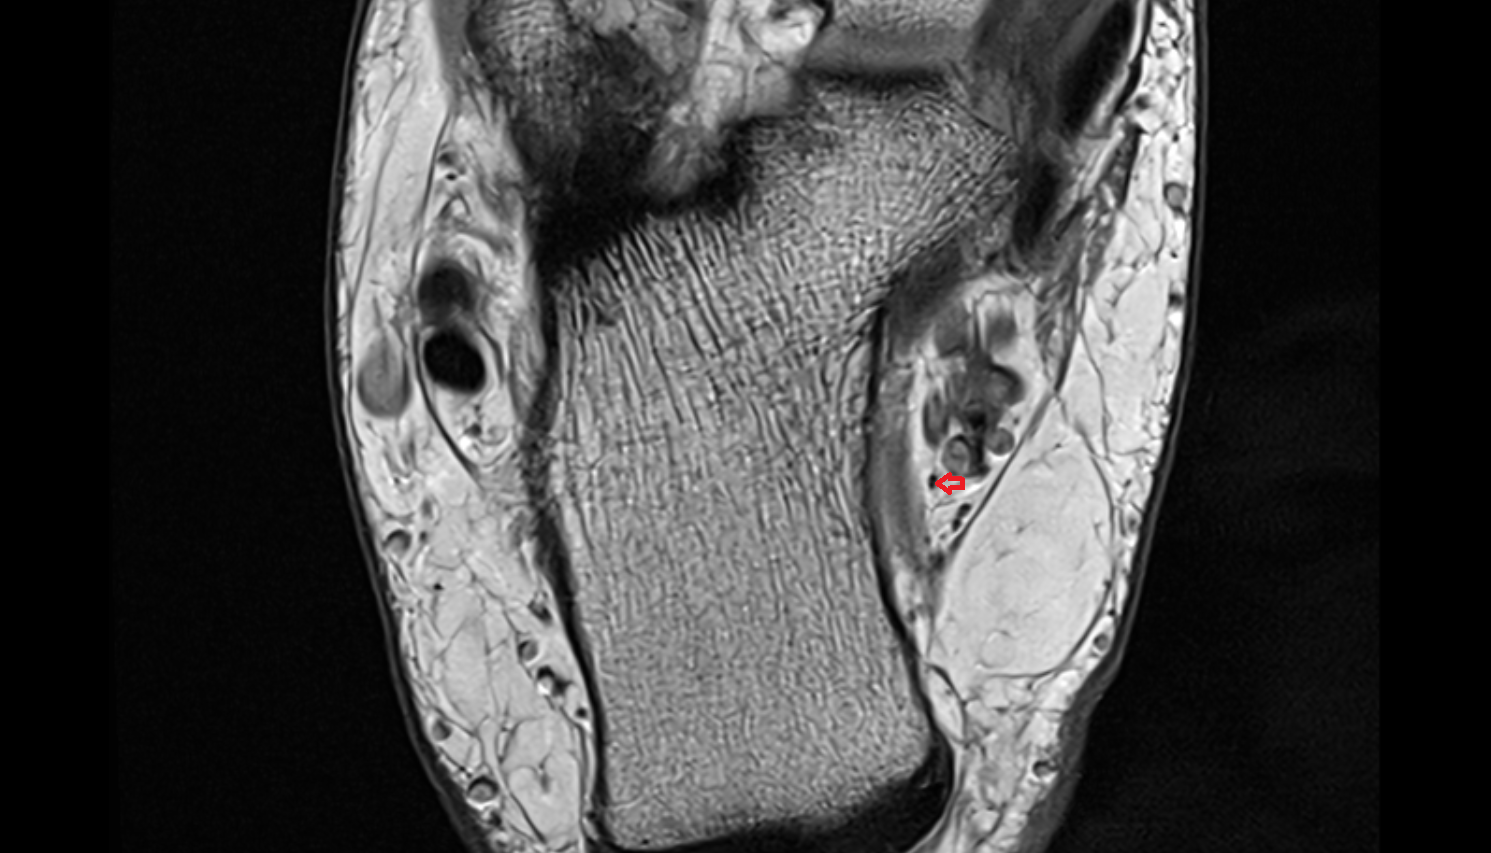

MRI images

Inferior calcaneal nerve (Baxter’s nerve) axial cross sectional anatomy 3T MRI AI enhanced radiology image-img-00000-00000